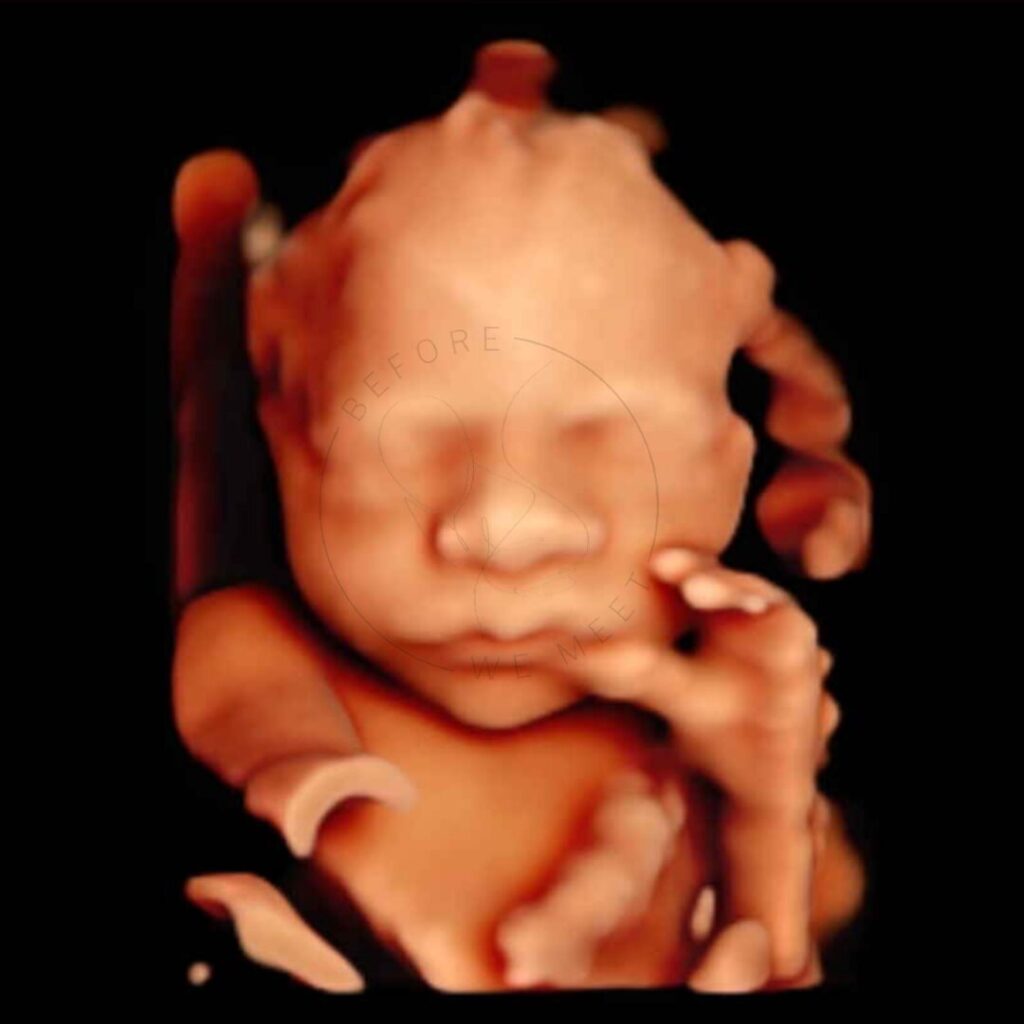

Veel ouders kiezen voor een pretecho als herinnering aan de zwangerschap of om samen met familie of vrienden extra naar de baby te kijken. Bij een 3D- of 4D-echo zien we duidelijk het gezichtje in kleur en zien we soms een lachje of een gaapje!

Een 3D/4D echo is éxtra bijzonder doordat we de baby met al zijn of haar details kunnen zien in stilstaande en bewegende beelden. Op wie lijkt zijn/haar neusje? Heeft hij/zij al bolle wangetjes? Of misschien zien we de baby zelfs wel drinken of lachen? Het laat jou (en ons!) verwonderen hoe magisch het nieuwe leven dat in je buik groeit is!

Iedere periode van de zwangerschap vinden wij even bijzonder, juist omdat je per maand zoveel verschil kunt zien. Echter is herkenning van het gezichtje het mooiste tussen de 24e en 30e week van de zwangerschap en afhankelijk van hoe de baby in je buik ligt, of hij/zij zich verstopt achter handjes, voetjes of de placenta en hoeveel vruchtwater er aanwezig is. Mocht het daardoor niet lukken om de baby goed in beeld te krijgen dan mag je nogmaals kosteloos terugkomen voor een echo van 20 minuten.